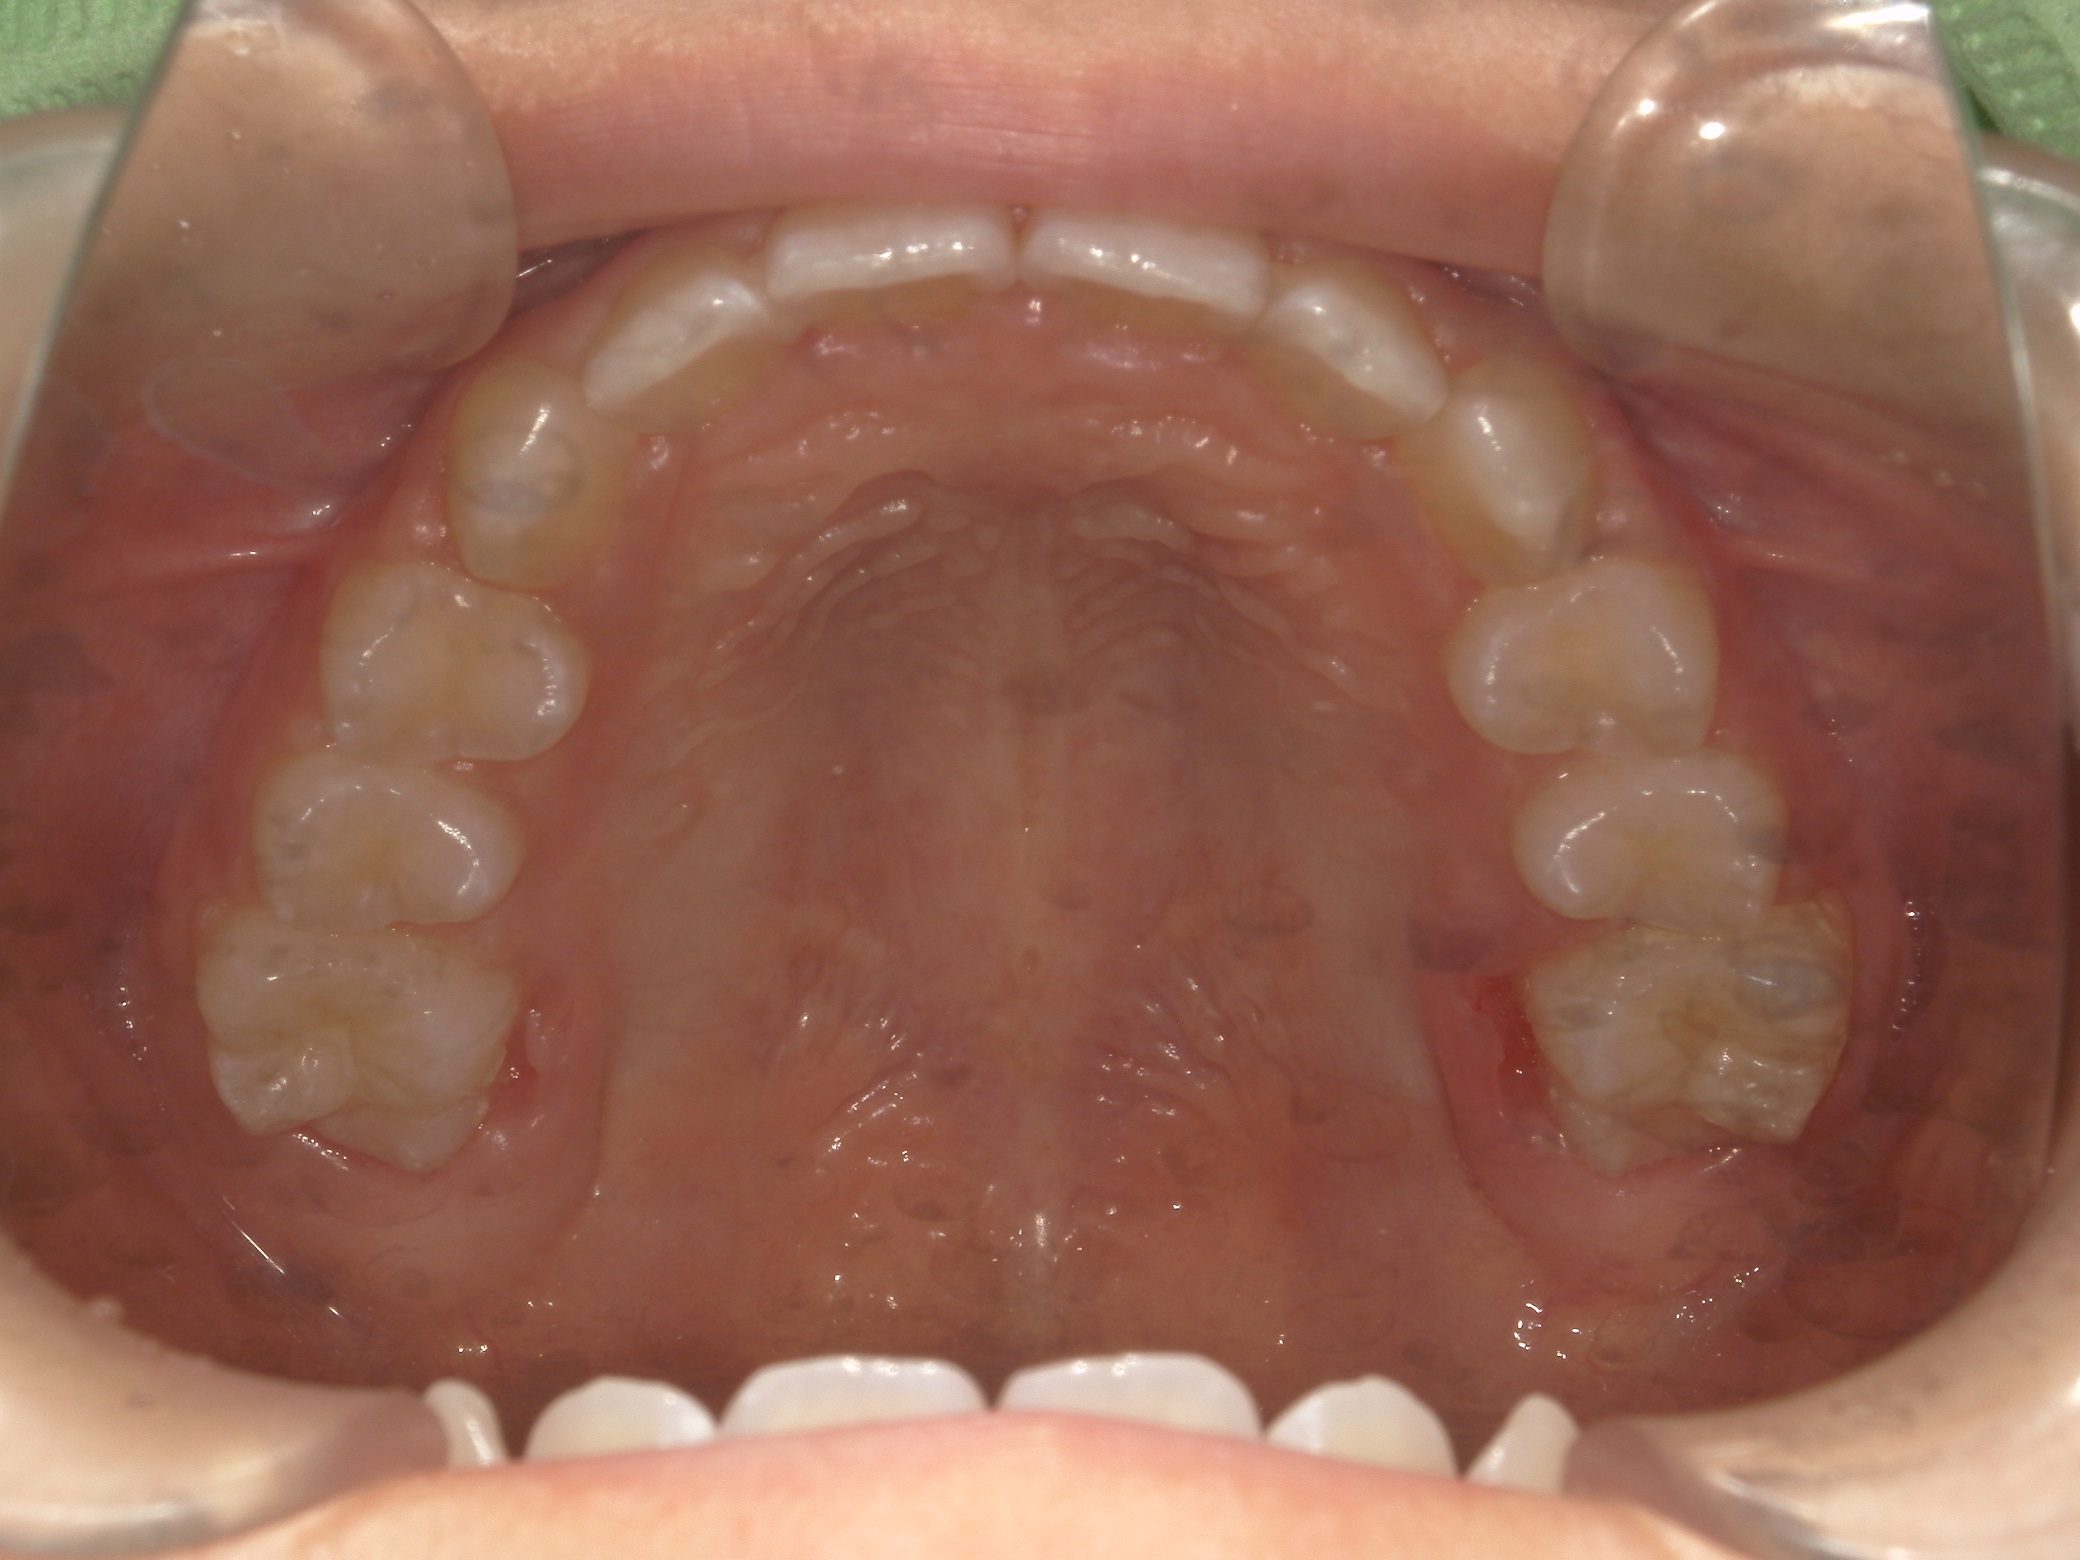

【小学生】マイオブレース矯正 上顎前突(出っ歯)と叢生(でこぼこ)を改善

マイオブレース

でこぼこ

出っ歯

過蓋咬合

非抜歯

1期治療のみで改善

Before

After

治療期間

1.5年

治療開始

8歳

種類

マイオブレース矯正

使用装置

機能矯正装置 3Dリンガルアーチ

コメント

とてもきっちり取り組んでくれたのでスムーズに治りました。

終了して数年たちますが、現在もしっかり維持してくれています。